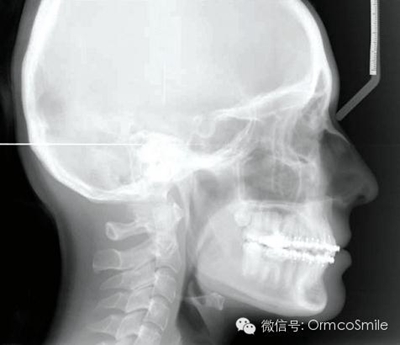

頭影測(cè)量分析顯示,SNA為80.9°,SNB為79.5°,ANB為1.4°,SN-GoMe角為25.5°,下切牙到NA的角度為22°、距離為4mm,上頜切牙與NA角度為18°、距離為4mm,上唇在E線后5mm,下唇在E線后3mm,鼻唇角為110°。

經(jīng)測(cè)量,上頜第一磨牙遠(yuǎn)中移動(dòng)3.5mm,達(dá)到磨牙Ⅰ類關(guān)系,同時(shí)壓低2mm,而第一前磨牙和上頜切牙沒有明顯的移動(dòng)。上頜第一前磨牙有3°的輕度前傾,這可能是由于上頜只植入了1顆螺紋釘?shù)脑颍髡叻治霾捎脙深w螺紋釘可以減少這種副作用。在上頜磨牙遠(yuǎn)中移動(dòng)過程中,下頜平面角減少了1°,且其持續(xù)到正畸治療結(jié)束。上頜牙弓寬度有輕度擴(kuò)大。